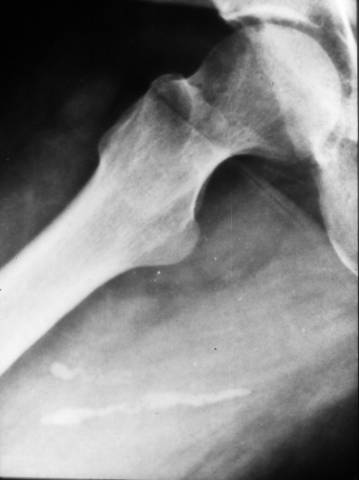

Calcified Guinea Worm